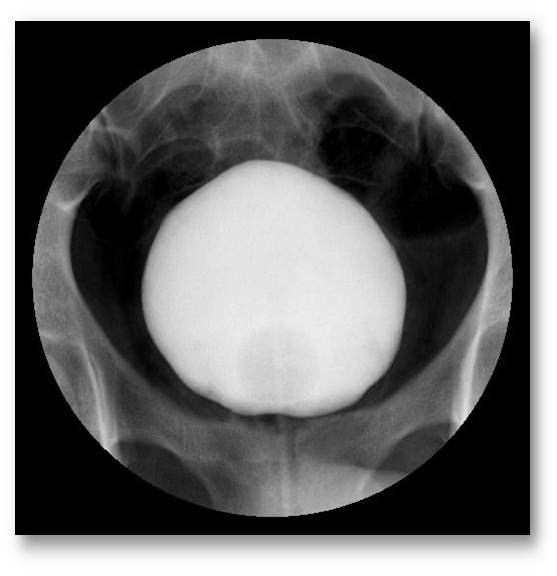

КТ при нейрогенном мочевом пузыре: что нужно знать?